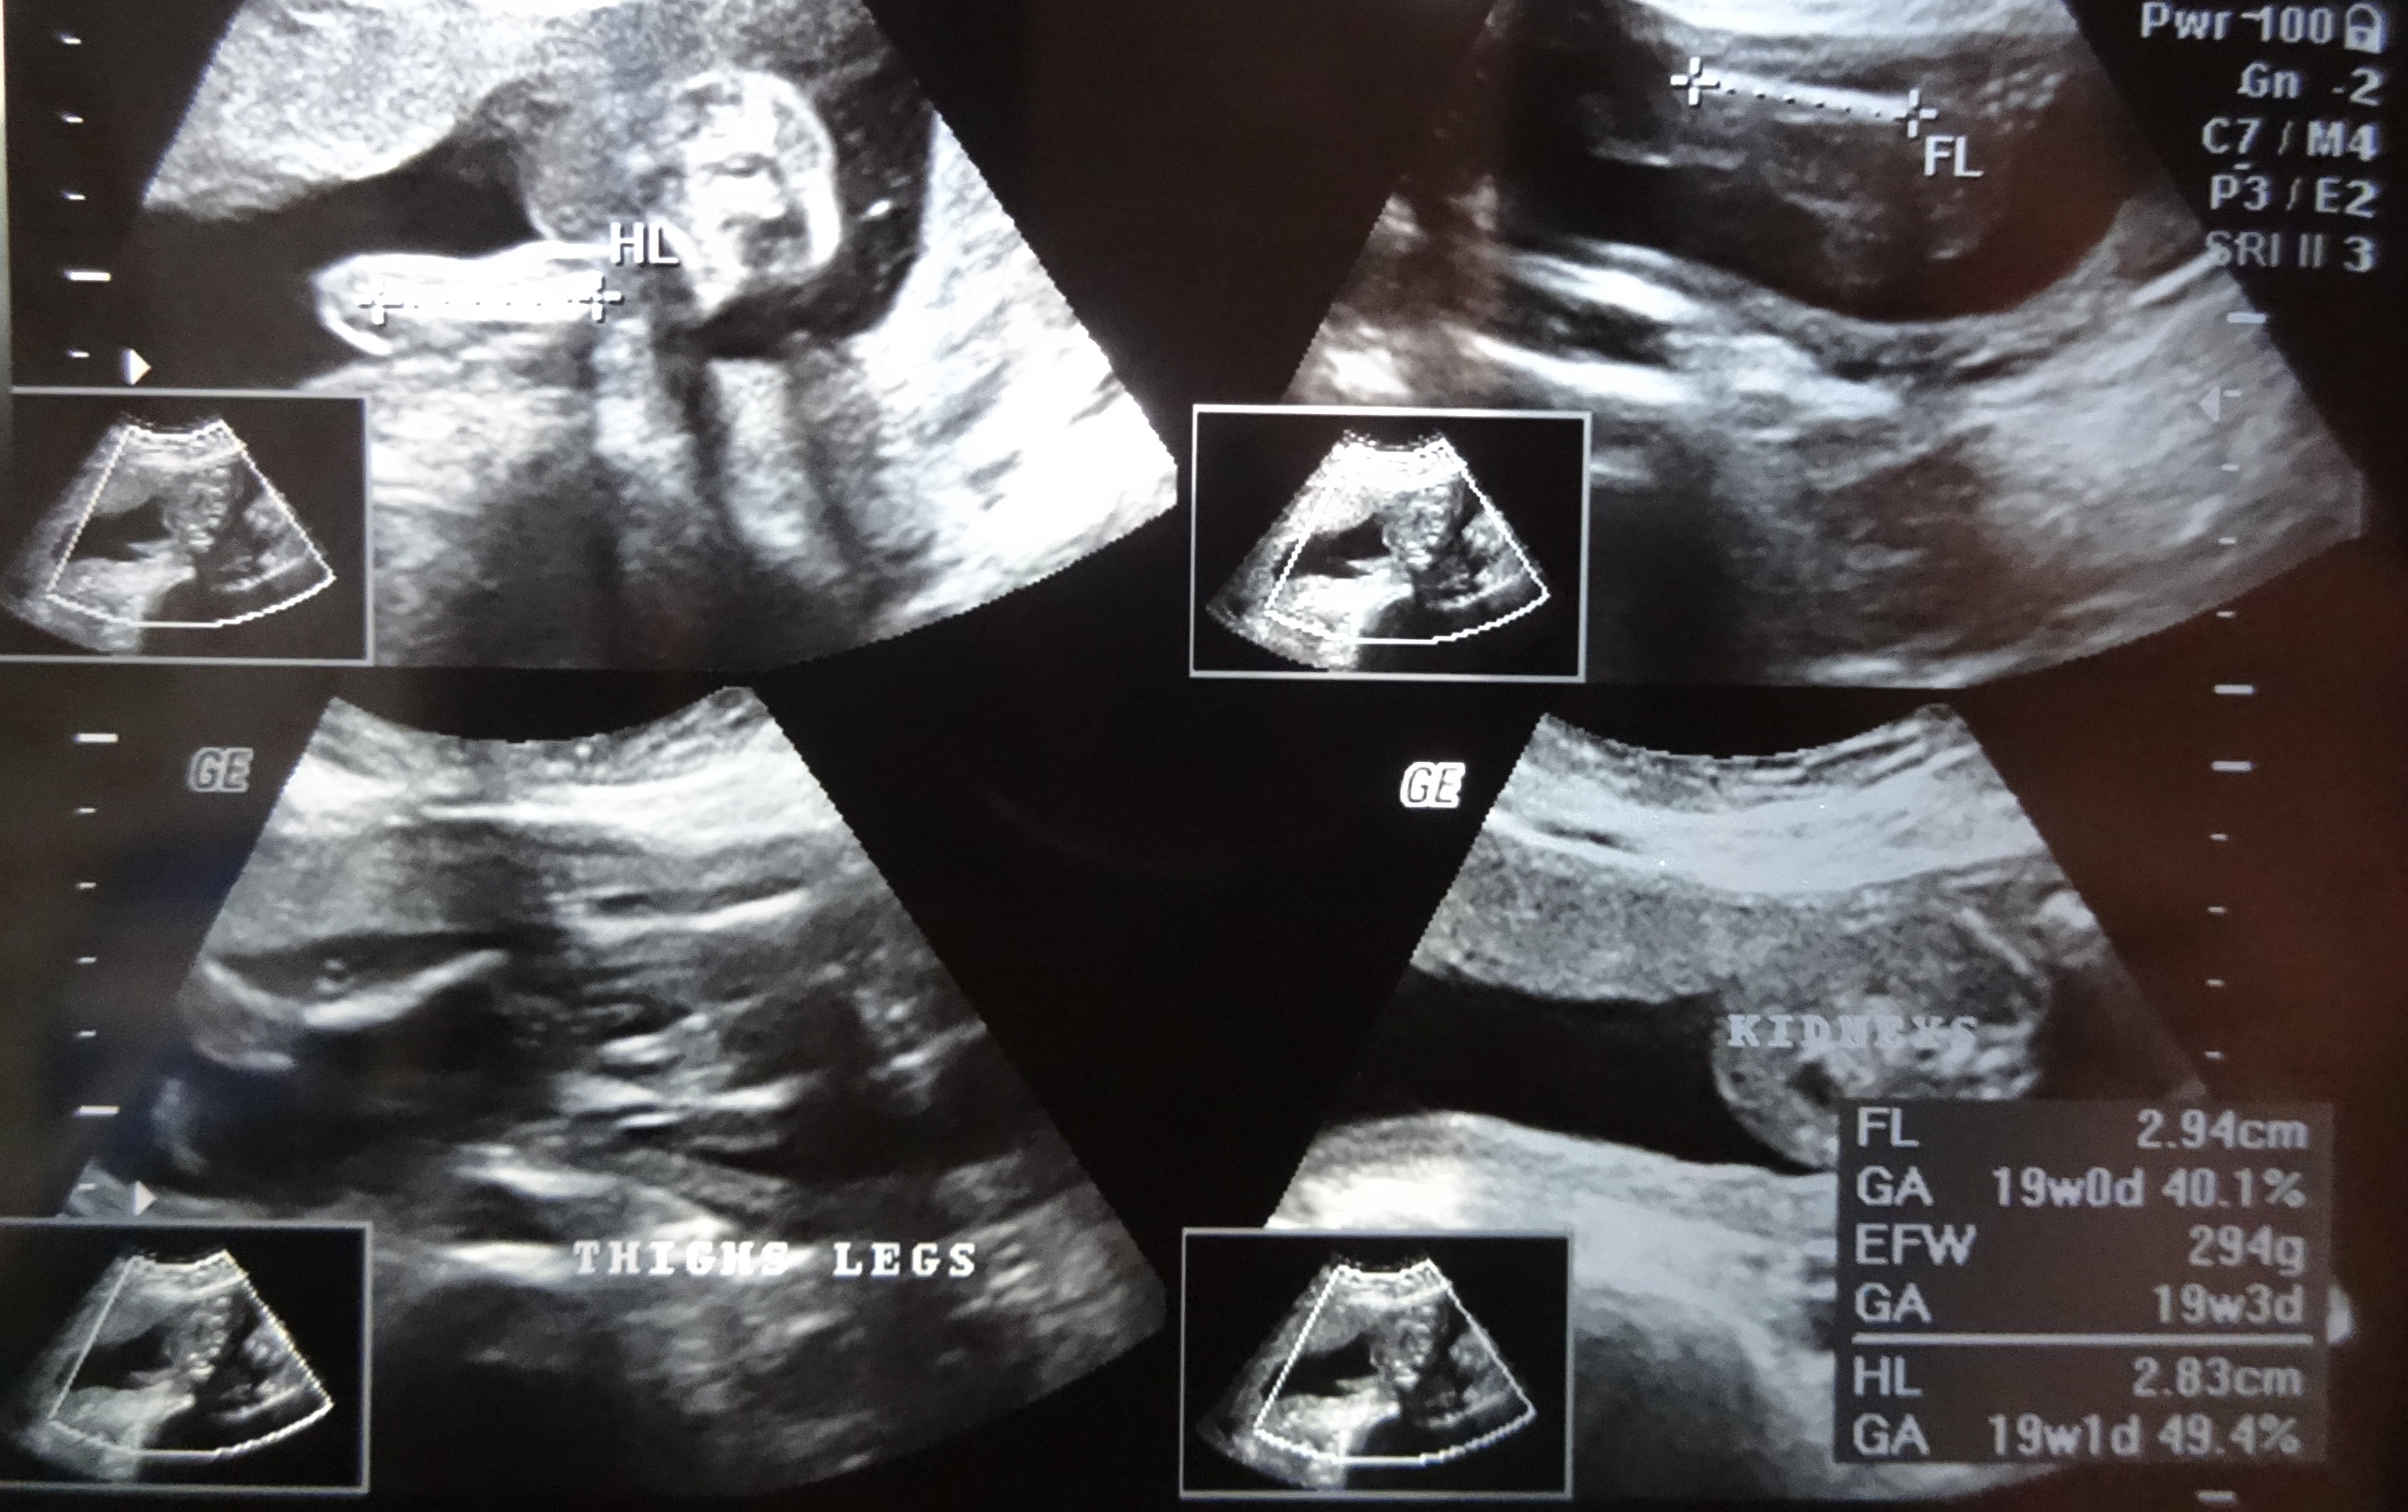

Attachment 21188

can anyone please guess mine ? this one is a 21 W 6 D picture , side view. Not sure what to look at where :-/

i am a total new to these forums, just trying a shot at it. Here is another one, of thighs & legs,,,, if that can help any guessesAttachment 21189